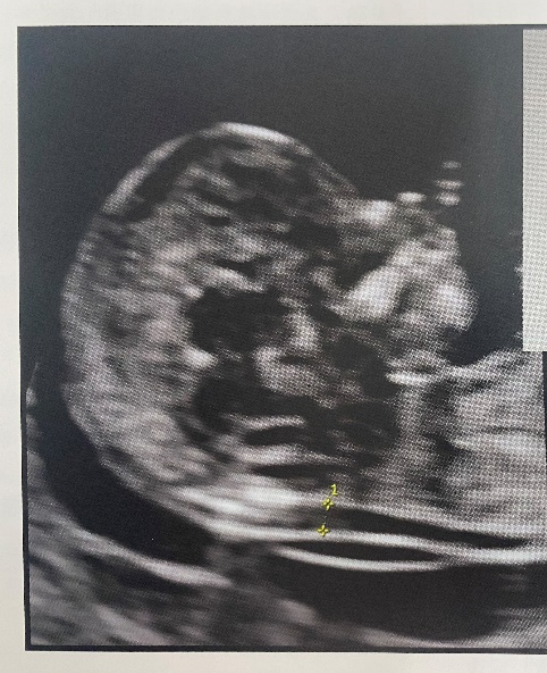

【请教】胎儿颈项透明层是否异常(又增加一个病例) [病例帖]

nt检查是应用超声(经腹)测量胎儿颈项透明带厚度,nt检查的正常范围为

颈项透明层 > 2.5 mm,孩子还能要吗?

5mm时判断为正常,当胎儿nt值(颈后透明带)大于或等于3mm时,可判断为颈